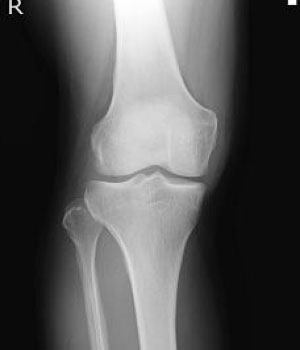

エックス線を利用して検査をするいわゆる“レントゲン撮影”です。

胸部、腹部、全身の骨の撮影を行います。心臓の大きさや肺の異常陰影、ガスの状態や骨の形、骨折の有無、関節の状態などがわかります。

当院ではフラットパネル(FPD)というシステムを導入し従来よりもエックス線の感度が高く低被ばくで撮影ができるようになりました。撮影効率も向上し撮影待ち時間も短縮しています。